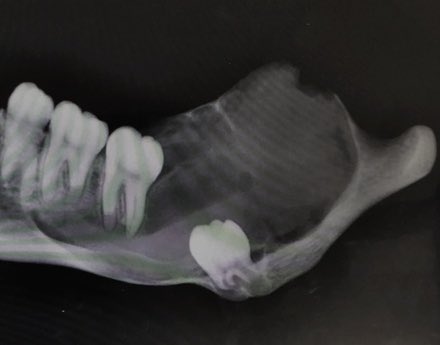

تكيس الفك الأكثر حصولاً هو ال

Dentigerous Cyst

ويتكون خلال النمو عند انفصال الغشاء المحيط بالسن عن تاج السن قبل بروزه داخل الفم مما يؤدي الى تكون ما يطلق عليه كيس "دهني" والذي يمكن ان يتمدد لدرجات مختلفة قبل ان يتم تشخيصه